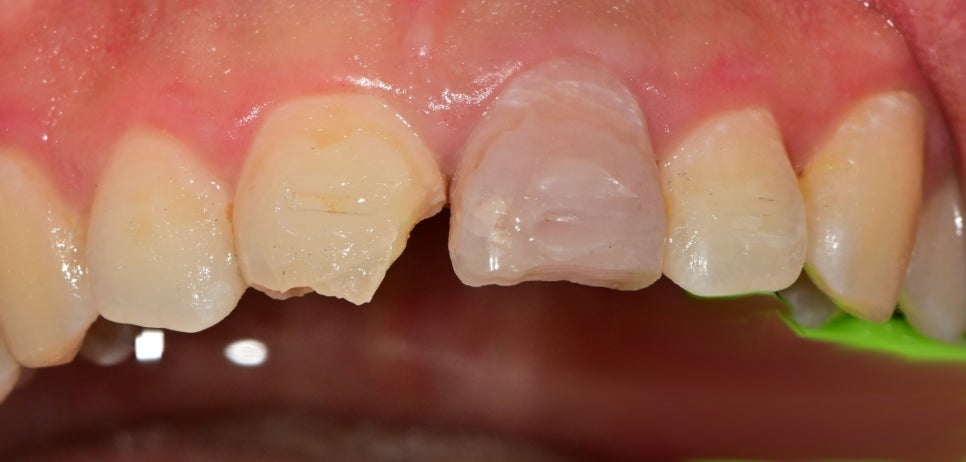

2주 후 체크를 했습니다.

고정 장치를 제거하고 치료 중간에 사진이긴 합니다만

치아의 흔들림은 이제 잡혔지만

가운데 고정했던 치아의 색이 어둡게 변한 것을 볼 수 있습니다.

일반적으로 치아의 신경 즉, 치수 괴사가 일어나게 되면 치아가 어두워집니다.

이것은 이미 생활력을 잃었기 때문에 해당치아는 신경치료 후 크라운치료를 결정했습니다. 그 옆의 치아 또한 파절편에 컸고 주변 금이 가있는 치아파절편들이 많지만 신경의 생활력은 살아있어서 신경치료 없이 크라운치료로 마무리하기로 했습니다.